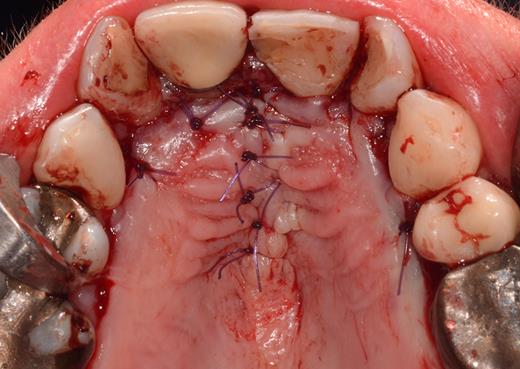

After a sulcular incision on the palatal side from teeth 15 to 25 and an incision in the midline of the palate omitting the incisive papilla and the two orifices of the NPD, two full-thickness mucoperiosteal flaps were raised. Thereafter, the incisive papilla and the whole contents of the incisive canal were enucleated (Figs 4–6). The bony incisive canal was filled with autologous bone harvested from the palatal region (bone scraper) (Fig. 7). A tension-free primary wound closure was achieved by moving the palatal flaps to the midline using single button and interdental vertical mattress sutures (Monocryl 4-0, Ethicon, Johnson & Johnson, USA) (Fig. 8). To avoid wound dehiscence and hematoma, an iodoforme gauze and a palatal plate were applied (Fig. 9). The patient was instructed to rinse three times a day with 0.1% chlorhexidine (formula hospitalis) for 2 weeks postoperatively. Sutures were removed after 14 days.

Preparation of the soft tissue of the incisive canal and the incisive papilla.